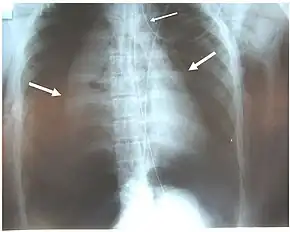

Chest x-ray is the initial imaging technique used to diagnose TBI.[17] The film may not have any signs in an otherwise asymptomatic patient.[15] Indications of TBI seen on radiographs include deformity in the trachea or a defect in the tracheal wall.[17] Radiography may also show cervical emphysema, air in the tissues of the neck.[2] X-rays may also show accompanying injuries and signs such as fractures and subcutaneous emphysema.[2] If subcutaneous emphysema occurs and the hyoid bone appears in an X-ray to be sitting unusually high in the throat, it may be an indication that the trachea has been severed.[4] TBI is also suspected if an endotracheal tube appears in an X-ray to be out of place, or if its cuff appears to be more full than normal or to protrude through a tear in the airway.[17] If a bronchus is torn all the way around, the lung may collapse outward toward the chest wall (rather than inward, as it usually does in pneumothorax) because it loses the attachment to the bronchus which normally holds it toward the center.[6] In a person lying face-up, the lung collapses toward the diaphragm and the back.[23] This sign, described in 1969, is called fallen lung sign and is pathognomonic of TBI (that is, it is diagnostic for TBI because it does not occur in other conditions); however it occurs only rarely.[6] In as many as one in five cases, people with blunt trauma and TBI have no signs of the injury on chest X-ray.[23] CT scanning detects over 90% of TBI resulting from blunt trauma,[3] but neither X-ray nor CT are a replacement for bronchoscopy.[6]